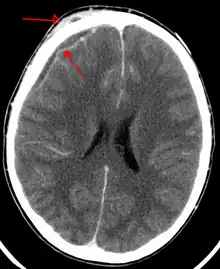

An abscess that has led to an intracranial subdural empyema as seen on CT

Subdural empyema is a form of empyema – a collection of pus, in the subdural space.

Bacterial or occasionally fungal infection of the skull bones or air sinuses can spread to the subdural space, producing a subdural empyema. The underlying arachnoid and subarachnoid spaces are usually unaffected, but a large subdural empyema may produce a mass effect. Further, a thrombophlebitis may develop in the bridging veins that cross the subdural space, resulting in venous occlusion and infarction of the brain. With treatment, including surgical drainage, resolution of the empyema occurs from the dural side, and, if it is complete, a thickened dura may be the only residual finding. Symptoms include those referable to the source of the infection. In addition, most patients are febrile, with headache and neck stiffness, and, if untreated, may develop focal neurologic signs, lethargy, and coma. The CSF profile is similar to that seen in brain abscesses, because both are parameningeal infectious processes. If diagnosis and treatment are prompt, complete recovery is usual.